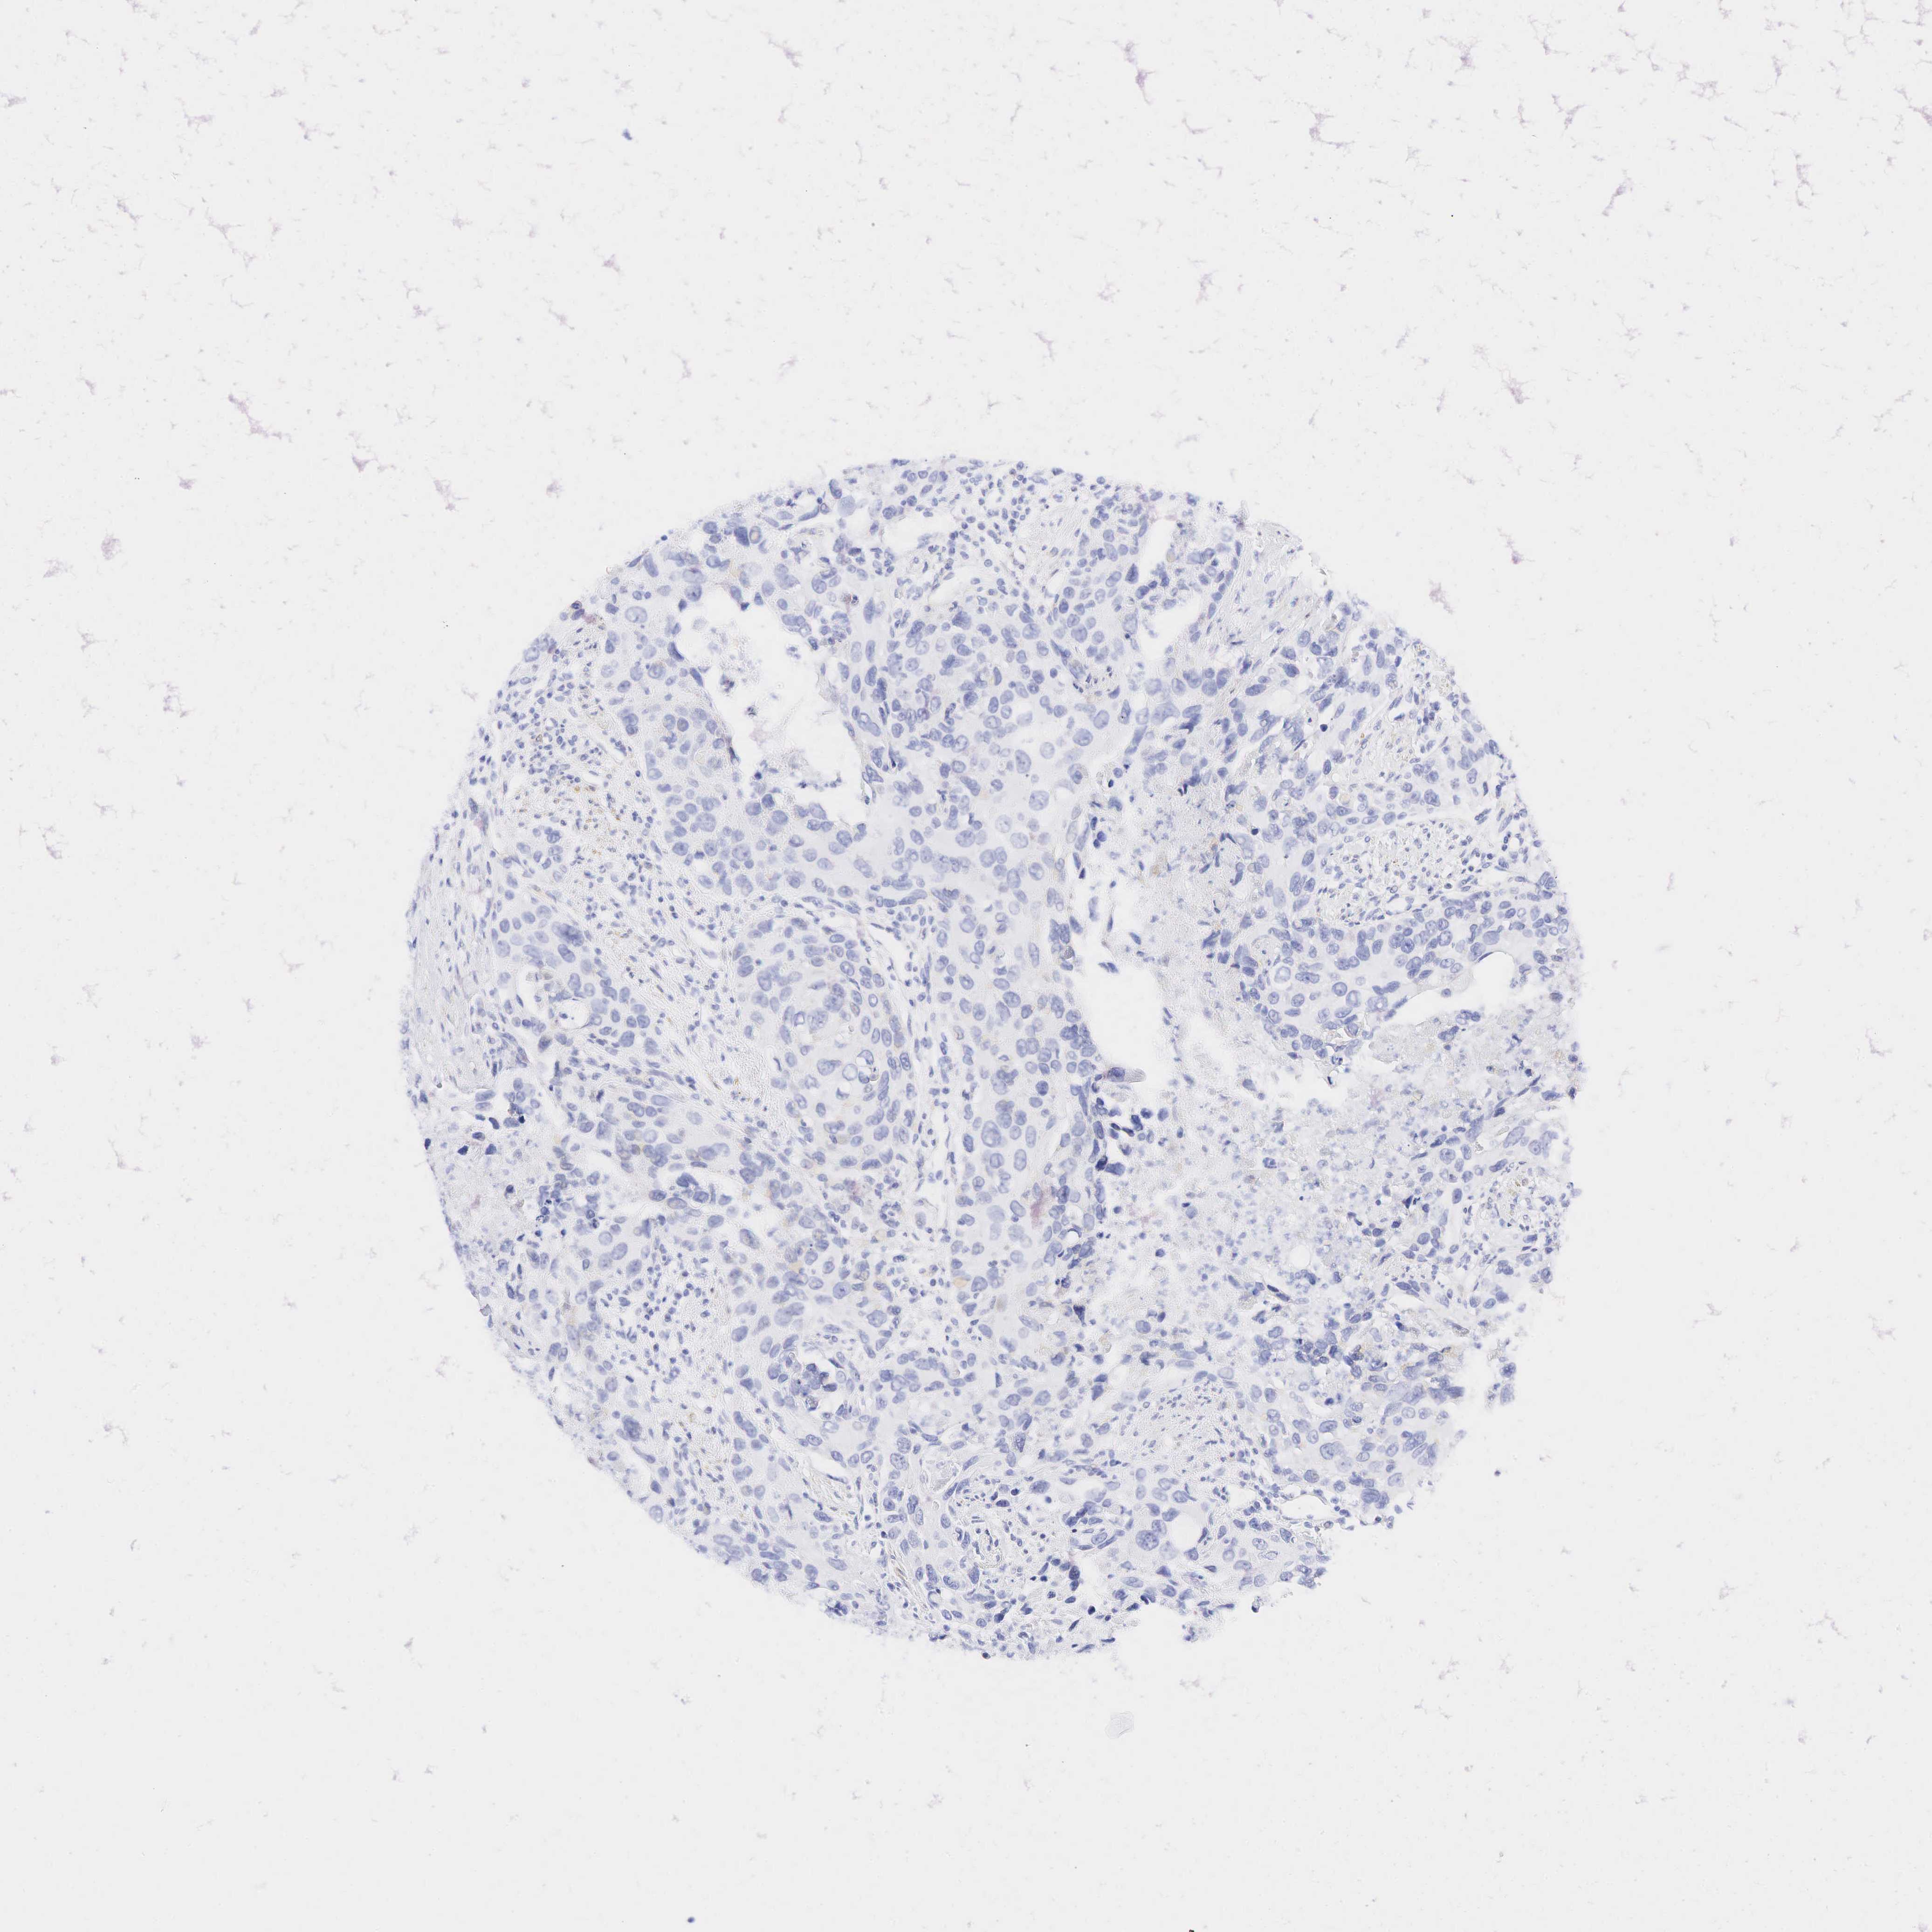

UROTHELIAL CANCER - Protein expressioni

A mouse-over function shows sample information and annotation data. Click on an image to view it in a full screen mode. Samples can be filtered based on level of antibody staining by selecting one or several of the following categories: high, medium, low and not detected. The assay and annotation is described here.

Antibody stainingi

Antibody staining in the annotated cell types in the current human tissue is reported as not detected, low, medium, or high, based on conventional immunohistochemistry profiling in selected tissues. This score is based on the combination of the staining intensity and fraction of stained cells.

Each image is clickable and will lead to virtual microscopy that enables deeper exploration of all samples and also displays staining intensity scores, fraction scores and subcellular localization as well as patient and tissue information for each sample.

Antibody HPA008066

Antibody HPA017330

Antibody CAB000006

Urothelial carcinoma, Low grade

Urothelial carcinoma, High grade